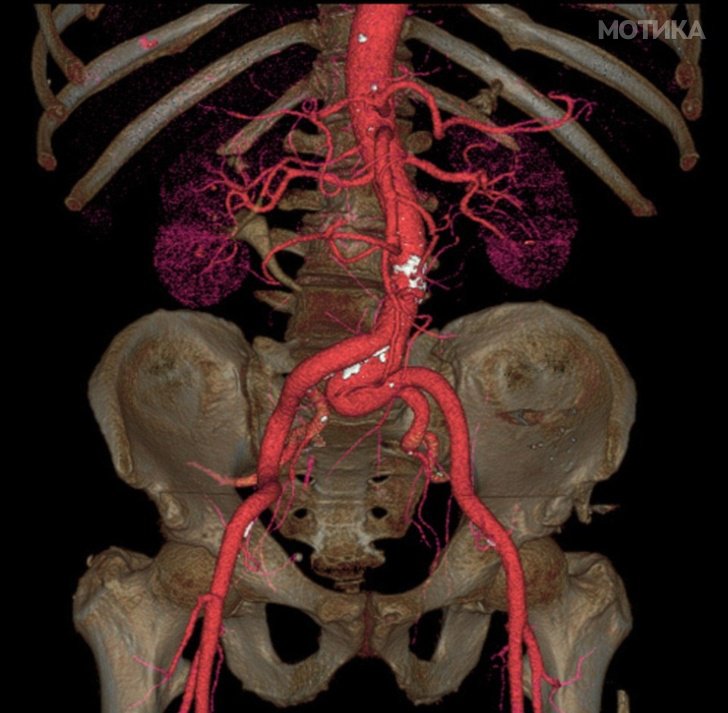

16. Аорта – најголемата артерија на нашето тело.